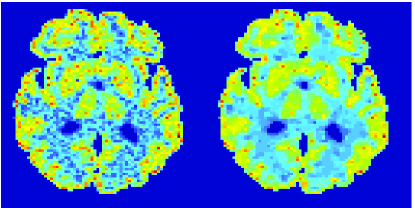

In the images shown in the figures we illustrate the calculated uptake rates of the FDG. Images for the CMRGlc can be obtained by directly scaling . In figure 1 we compare the result of using Patlak and TV-Patlak for estimating the uptake rates with respect to no noise, noise in the input function, Poisson noise in the sinogram, and finally with respect to the case in which the irreversibility assumption is violated but without noise in the sinogram or input data. In each case the histogram of the relative errors is given on the left, the Patlak image in the middle and the TV-Patlak on the right. The different scales in the histograms are due to the total number of results illustrated. When there is no noise (triples and ) the histogram illustrates results over all voxels but only one simulation, while for the noisy simulations the results are for all voxels over all realizations of the noise. The TV-Patlak images are more homogeneous in all cases and the relative errors are smaller. The figures clearly show the improvements of employing the TV-Patlak method as compared to using Patlak independently for each voxel. This is confirmed in figure 2 in which images with noise in the sinogram, positive and different noise levels in the input function are shown.

In figures 3 and 4 we illustrate the uptake rates and relative error in the uptake rates, respectively, calculated by Patlak, TV-Patlak, Patlak-GF and Patlak-MF for one simulated data case , i.e. , noise in the input function and Poisson noise in the sinograms. The uptake rate image generated by Patlak-MF is visually smoother than that by TV-Patlak, but the equivalent histograms show that the relative error is higher for Patlak-MF than for TV-Patlak; the Patlak-MF image is over-smoothed.